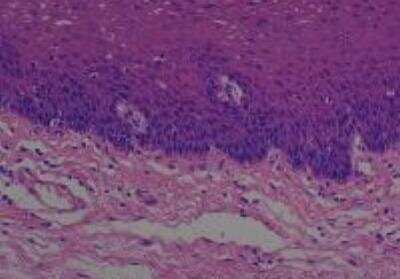

Hematoxylin & Eosin Stain: Human Common Tissue MicroArray (Normal Adjacent) [NBP2-30215] - 102. Stomach